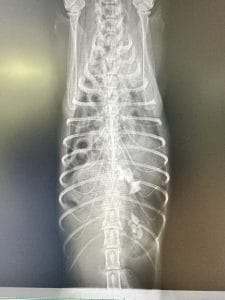

犬や猫の外傷性横隔膜ヘルニアとは?|実際の症例をもとに治療法を解説

横隔膜ヘルニアは横隔膜に穴が空き、腹腔内の臓器が胸腔へ移動してしまう危険な病気です。今回は事故などで起こる外傷性横隔膜ヘルニアについて、症状・診断・治療の流れを症例をもとに解説します。